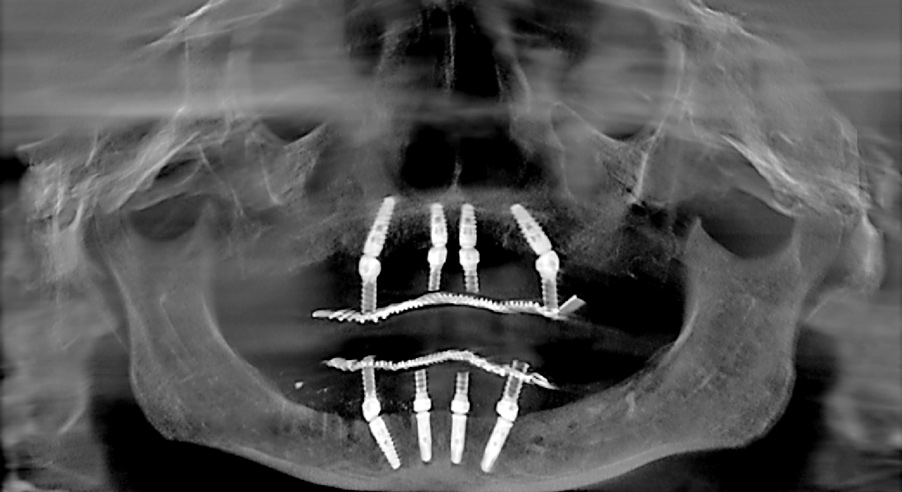

Fig 14. Postsurgical panoramic radiograph of All-on-4–style dental implant surgery with dental implants engaging cortical bone at the inferior border of the mandible.

Figure 14

Fig 15. Cross-sectional CBCT scan slice from Figure 14 showing apical engagement of the dental implant with the dense cortical bone at the inferior border of the mandible.

Figure 15

When such instances occur, whether in the mandible or maxilla, the author first attempts to place a larger-diameter implant of the same length as the implant that failed to achieve high initial torque value. Should this adjustment prove ineffective, a longer implant of a larger diameter is then used. In the maxilla, the longer implant may engage the vomer or lateral piriform rims to achieve apical stability.13 In the mandible, the author achieves primary implant stability by engaging the cortical bone at the inferior border of the mandible with the apical portion of the dental implant (Figure 14 and Figure 15).